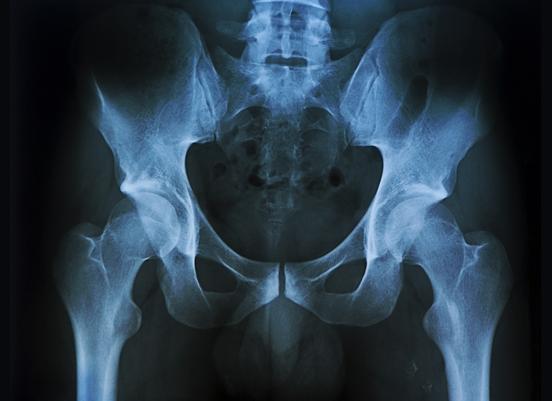

Рентген поясничного отдела позвоночника позволяет поставить точный диагноз, определить локализацию патологии, а также степень ее выраженности и характер патологических перемен. С его помощью можно выявить скопление жидкости, деформацию межпозвоночных дисков, изменение формы позвонков. Проведение процедуры назначается при подозрении на различные заболевания позвоночника и считается первоначальной диагностикой.

В норме позвонки должны размещаться друг над другом по вертикали, соответствовать по размеру, форме и количеству. Не должно наблюдаться отечности мягких тканей вокруг костей, искривлений, патологических образований, инородных предметов.

Отклонением от нормы считается наличие шпор кости на позвоночном столбе, деформация и искривление позвоночника, соскальзывание позвонков вперед или назад, перелом. Кроме этого, на снимке может быть обнаружен стеноз поясничного отдела, проявляющийся в сужении позвоночного канала. Также может наблюдаться смещение структур дисков за анатомические рамки, грыжевое выпячивание, пояснично-крестцовый радикулит.

В ходе проведения рентгенографии пояснично-крестцовой зоны медик оценивает состояние костной ткани больного, наличие жидкости, имеющиеся деформации межпозвоночных дисков. Дополнительно специалист может выявить различные патологии позвоночника.

Рентгенография позволяет выявить следующие проблемы в поясничной зоне:

- патологический изгиб позвоночника;

- опухолевые образования различной этиологии;

- износы костей и хрящей, которые приводят к сильным болевым ощущениям;

- остеопороз (истончение костной ткани);

- наличие спондилолистеза;

- стеноз (патологическое сужение позвоночника);

- болезни позвоночника на фоне заражения инфекцией;

- протрузии, грыжи межпозвонковых дисков и другие патологии.